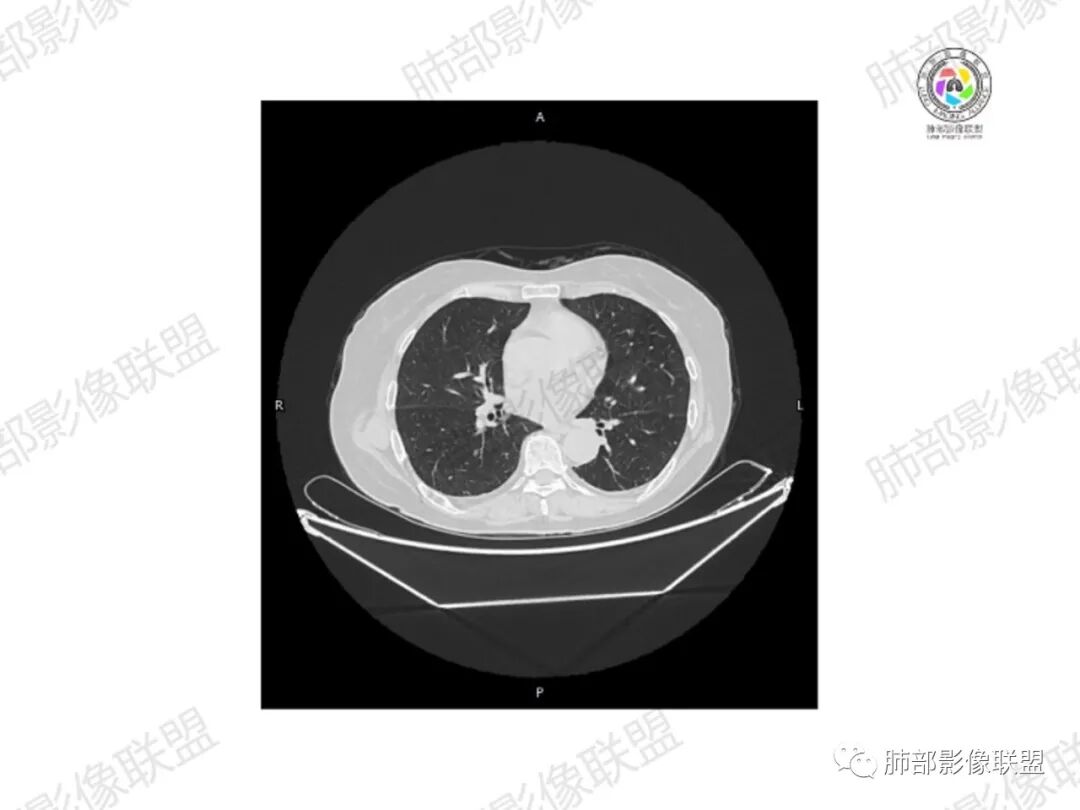

5.双肺多发类圆形结节影,边界清楚,随机分布,其间多见钙化密度影。

6.双肺门及纵隔未见肿大淋巴结。

3.双肺病灶符合转移瘤,伴有中央部分钙化者也以骨肉瘤转移较为多见。